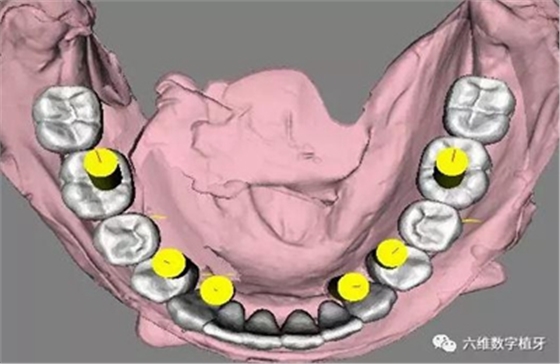

1. 選擇適當(dāng)?shù)姆N植體尺寸,精確的避開前牙區(qū)骨壁較薄的地方。

2. 預(yù)先在軟件里面進(jìn)行排牙,根據(jù)最終修復(fù)的效果精確放置種植體的位置。

3. 充分評估患者的骨質(zhì)條件,手術(shù)之前事先將固定的臨時義齒做好,進(jìn)行即刻負(fù)重。